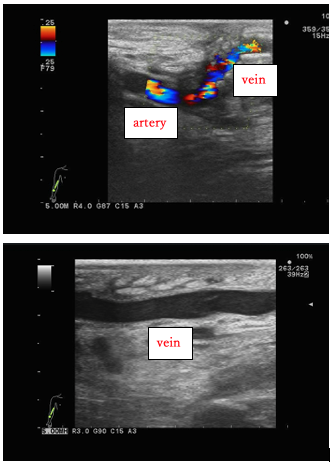

Figure 5. Ultrasound image 5 years after bypass surgery in Case 3. The anastomosis between the radial artery and the great saphenous vein is patent, and there is no stenosis in the grafted vein.